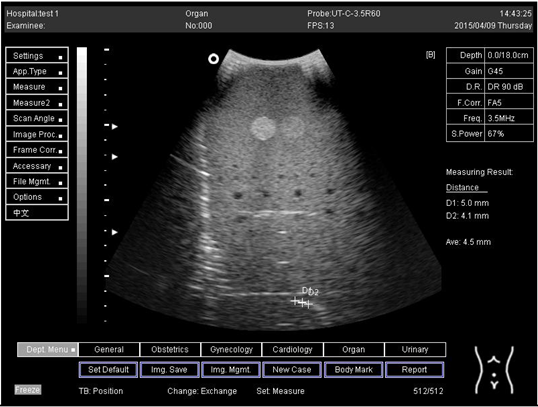

18.0Axial resolution

Biomimetics 07 00130 i019

D1 = 5.0

18.0Lateral resolution

Biomimetics 07 00130 i020

D2 = 4.1